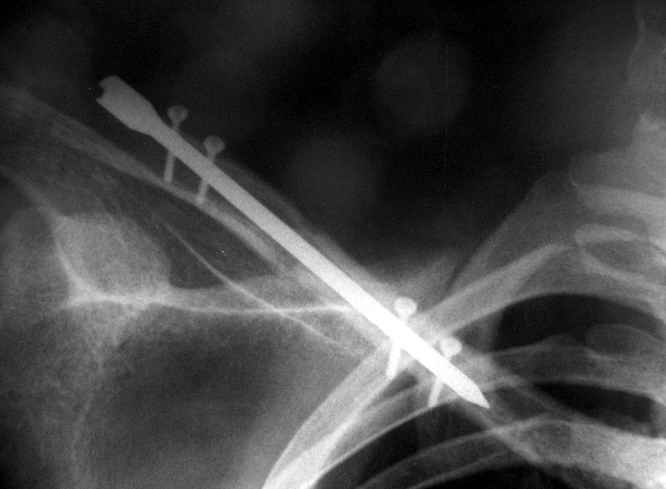

В приложении проект наших тезисов на съезд и клинический пример: Пациентка 23 лет поле неэффективного оперативного лечения (4 нед.) перелома ключицы спицей (была оперирована в С-Петербурге)(снимок после удаления спицы) и результат закрытого БИОС..